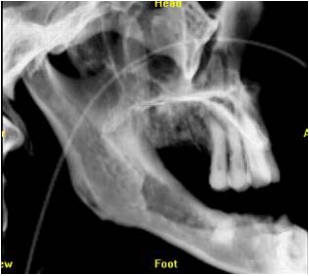

54.下列何者為最可能診斷? (A)LeFort I (B)LeFort II (C)LeFort III (D)Orbital blow out fracture

55. 承上題,下圖為病人之Waters’view X光檢查,下列敘述何者正確(箭頭表骨折處)? (A)兩側顴骨骨折 (B)勒福氏一型骨折 (C)勒福氏二型骨折合併左側顴骨骨折 (D)勒福氏三型骨折合併左側顴骨骨折

56.承上題,這位患者在當天接受緊急手術,下列為患者所接受之處置,其順序何者為適當? ①Intraoral approach over vestibular area ②Locate the fracture sites ③Arch bar splinting and intermaxillary fixation ④Miniplate and mini screws fixation ⑤Check the occlusion and close the wound (A)③→②→④→①→⑤ (B)①→②→③→④→⑤ (C)②→①→③→④→⑤ (D)③→①→②→④→⑤